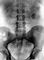

Рентгенологические методы являются основными в диагностике мочекаменной болезни . По обзорной рентгенограмме почти в 90% случаев могут быть установлены форма, величина, локализация и структура камня. Однако тень, подозрительная на конкремент, не требует дифференциальной диагностики только при коралловидном камне, заполняющем почечные лоханку и чашечки. Камни чашечек обычно имеют неправильную или округлую форму, камни лоханки — треугольную или округлую, мочеточника — цилиндрическую, мочевого пузыря — округлую. Наиболее интенсивную тень дают оксалатные камни, менее интенсивную — камни смешанного состава и фосфатные. До 10% камней (ураты, белковые, цистиновые и ксантиновые) являются рентгенонегативными и на обзорном снимке не видны. Для выявления камней, проецирующихся на изображение костей, делают прицельные рентгенограммы в косых и атипичных проекциях при рентгенотелевизионном просвечивании.

Диагностика мочекаменной болезни у детей, как и взрослых, базируется на результатах рентгенологического исследования (рис. 5). В детском возрасте рентгенонегативные камни встречаются гораздо реже, что ограничивает использование пневмопиелографии. Редки также различные рентгеноконтрастные образования лимфатических узлов, флеболиты и др., затрудняющие диагностику мочекаменной болезни . Размеры конкрементов, их форма, локализация часто не соответствуют глубине морфологических и функциональных изменений почки и мочевых путей.